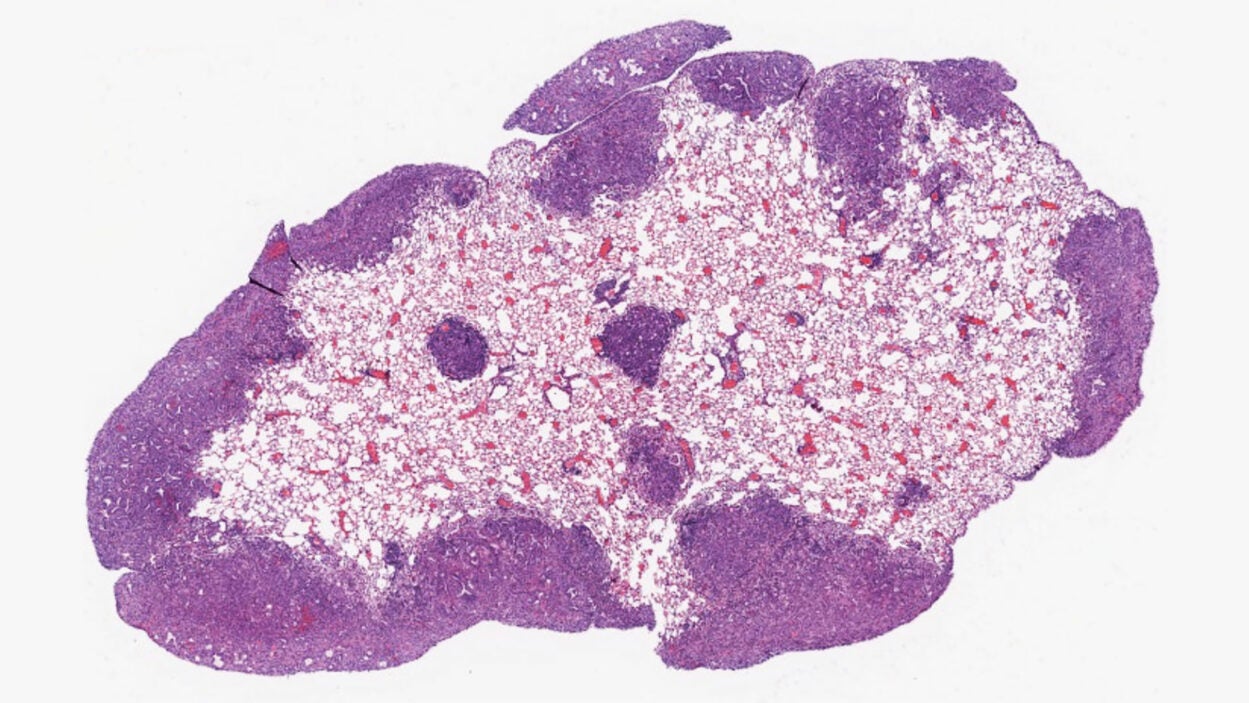

An angry peacock is no joke. Like the colorful bird and its tall tail feathers, cancer biology can make for some eye-catching images. Read the story »

That’s not the Starship Enterprise burning up in space. It’s an up-close look at precancerous pancreatic lesions and the mucus they produce. Read the story »